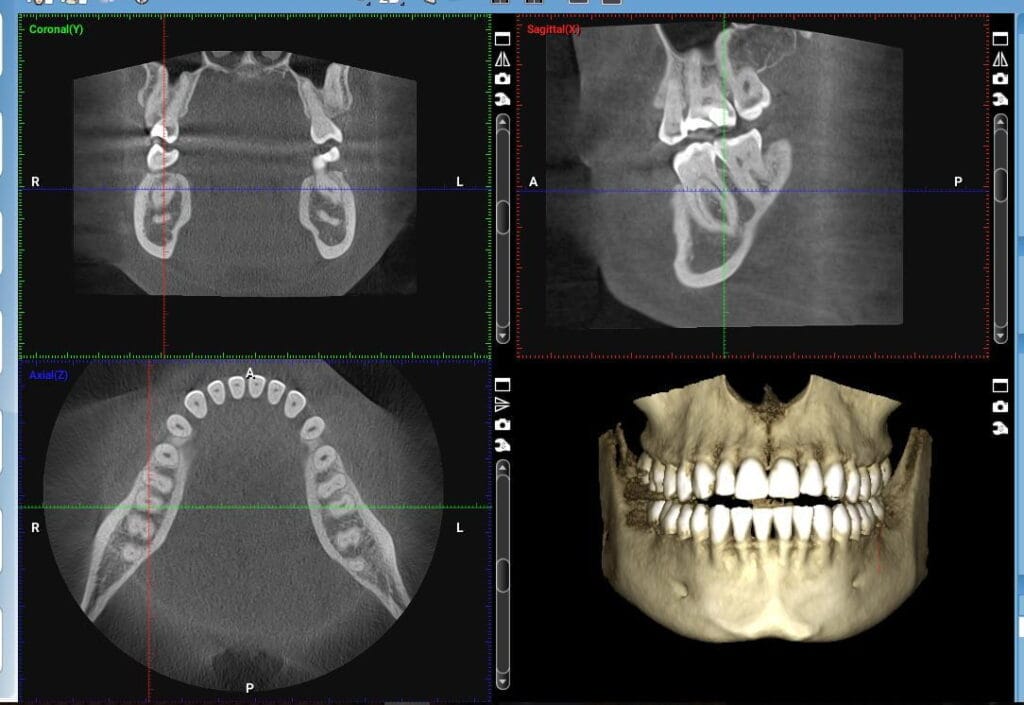

- 3D CT scan data

- Dental scan data

- Analysis of occlusion and jawbone anatomical structure